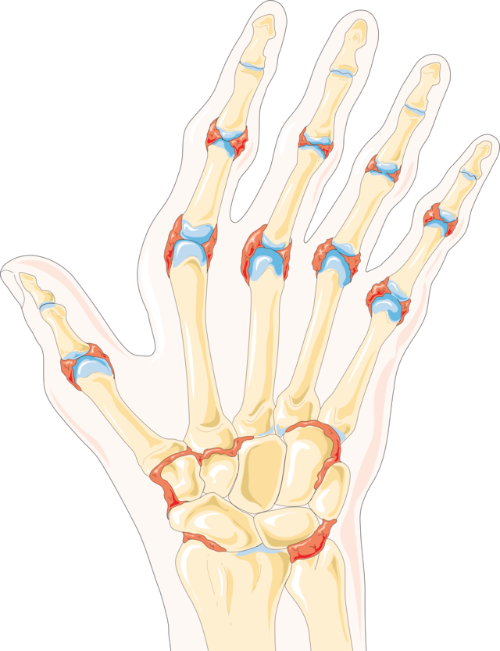

류마티스 관절염이란 뼈와 뼈를 잇는 관절에 발생하는 염증을 뜻합니다. 관절에는 관절액이라고 부르는 활액이 생깁니다. 이 활액이 관절을 둘러싸는 얇은 막이 바로 활막입니다. 류마티스 관절염은 여기에 염증이 생기는 것입니다.

류마티스 관절염은 손과 발처럼 관절이 여러 개 있는 곳에 염증이 생기기 때문에 염증성 전신 질환으로 불립니다.